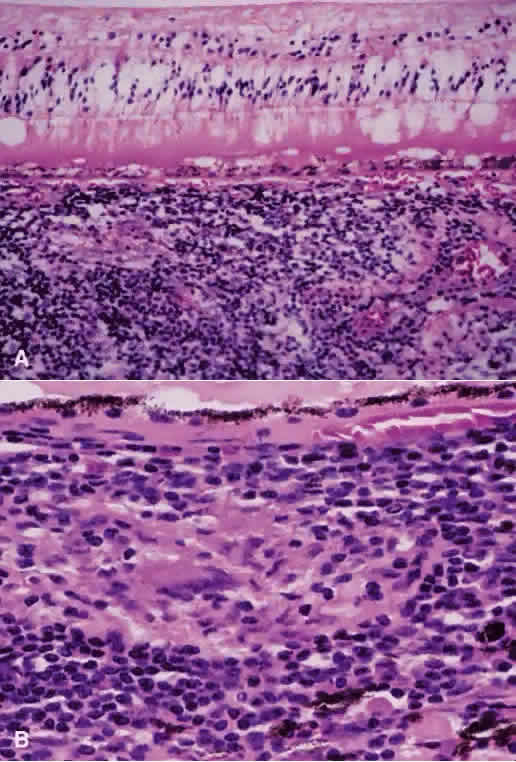

A Japanese national survey of BD has shown that ocular symptoms occur in 86% of patients with BD.40 Common clinical presentations include anterior uveitis with hypopyon (Fig. 4), vitritis, retinal vasculitis (Figs. 5 and 6), and chronic ischemic optic neuropathy. The hypopyon in BD has been shown to be composed of neutrophils41 and, in its later stages, lymphocytes as well.42 The disease tends to have a remitting-relapsing clinical course and carries a high potential for visually devastating complications.

Histopathologic data about Behçet's uveitis come from a few pathologic reports on enucleated, blind, painful eyes with chronic disease.43 Light microscopy usually shows a panuveitis with infiltrating polymorphonuclear leukocytes, lymphocytes, plasma cells, and macrophages (Fig. 7). Immunohistochemical studies have shown a perivascular choroidal infiltration of activated CD4+ , but not CD-8+ , T cells,44,45 as well as focal aggregates of B cells and plasma cells, with increased expression of cell adhesion molecules on vascular endothelial cells.43 These findings imply a mixture of cellular and humoral components in the pathogenesis of Behçet's ocular vasculitis, in which CD4+ cells activate B cells, resulting in enhanced local production of antibodies and immune complex deposition.43 However, the nature of the antigen in the complex is not known.

Fig. 7. Photomicrograph from eye of patient with Behçet's disease showing infiltration of retina with acute and chronic inflammatory cells, especially in the perivascular region (hematoxylin and eosin; × 400). (Photomicrograph courtesy of Professor Hajime Inomata, Kyushu University, Fukuoka, Japan.)